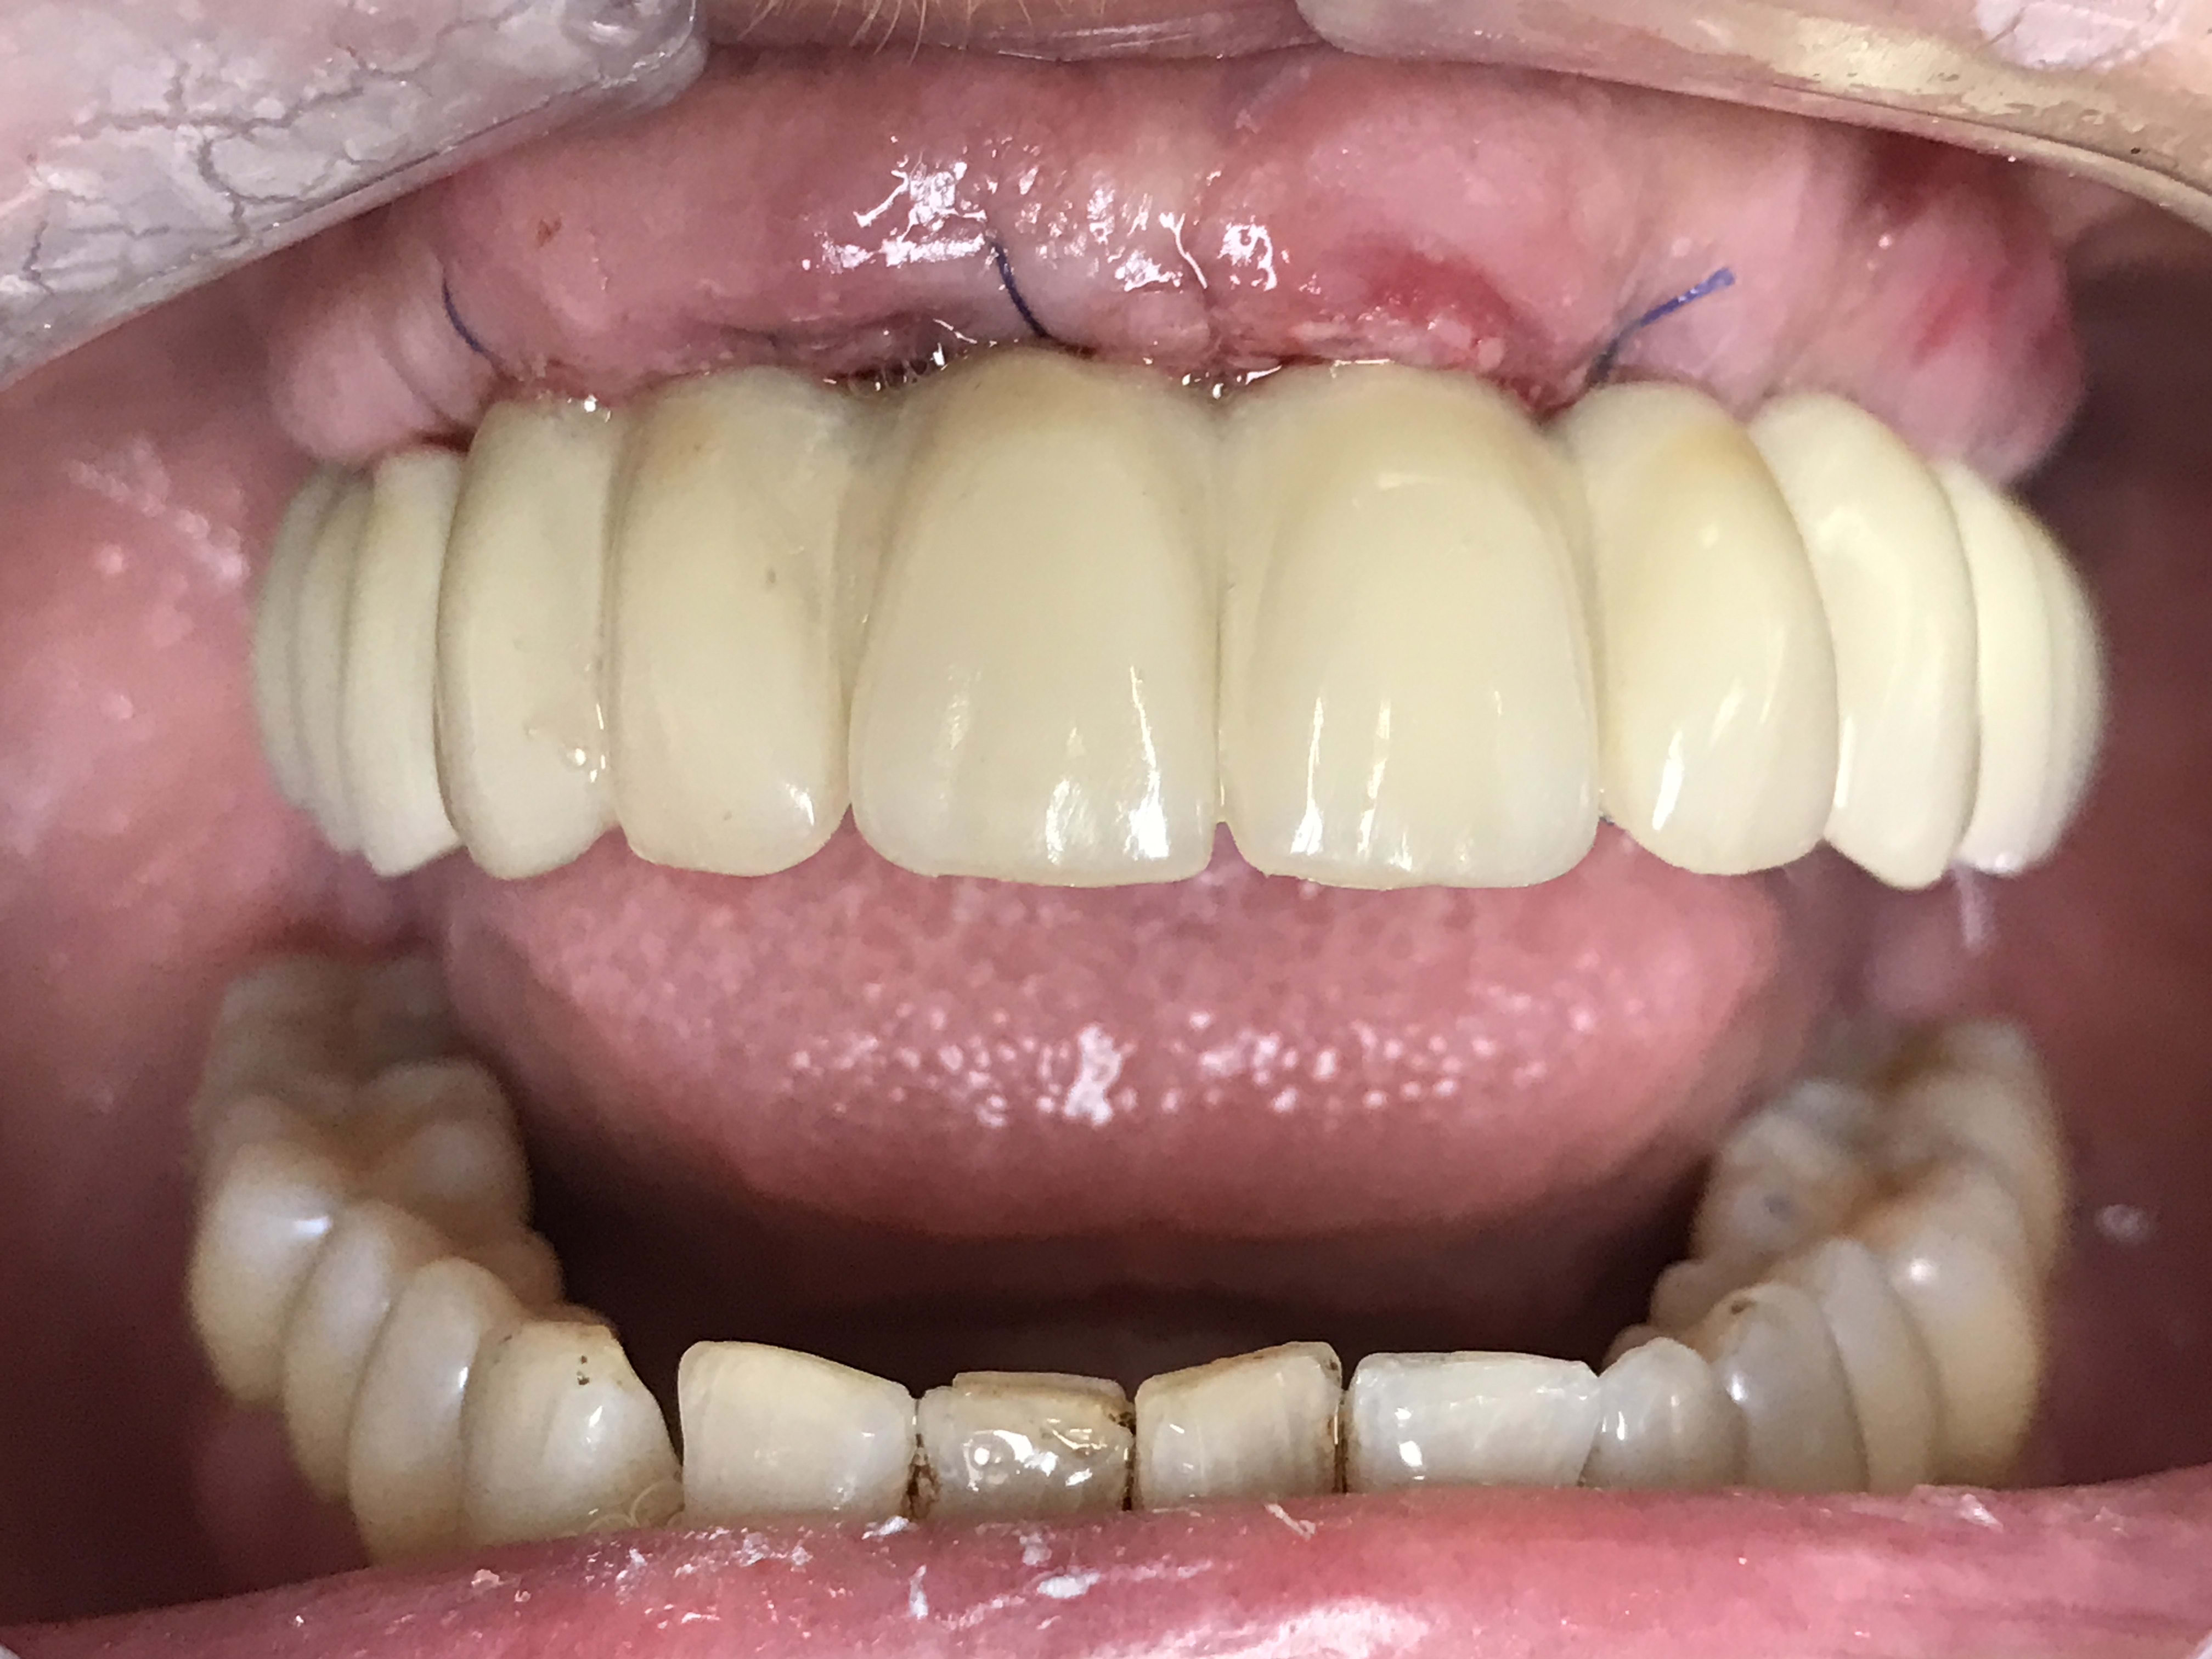

Désolé pour le retard, et aussi pour les photos de piètre qualité. J'ai les miroirs mais mon assistante n'a pas l'habitude de prendre des photos. C'était à j7 la gencive bien dégonflé. Heureusement on va refaire le bridge dans 4 mois.

Sinon j'ai eu mon deuxième cas de mise en charge cette semaine. Beaucoup moins de stress cette fois. Pose en 72h avec les délais de transports.